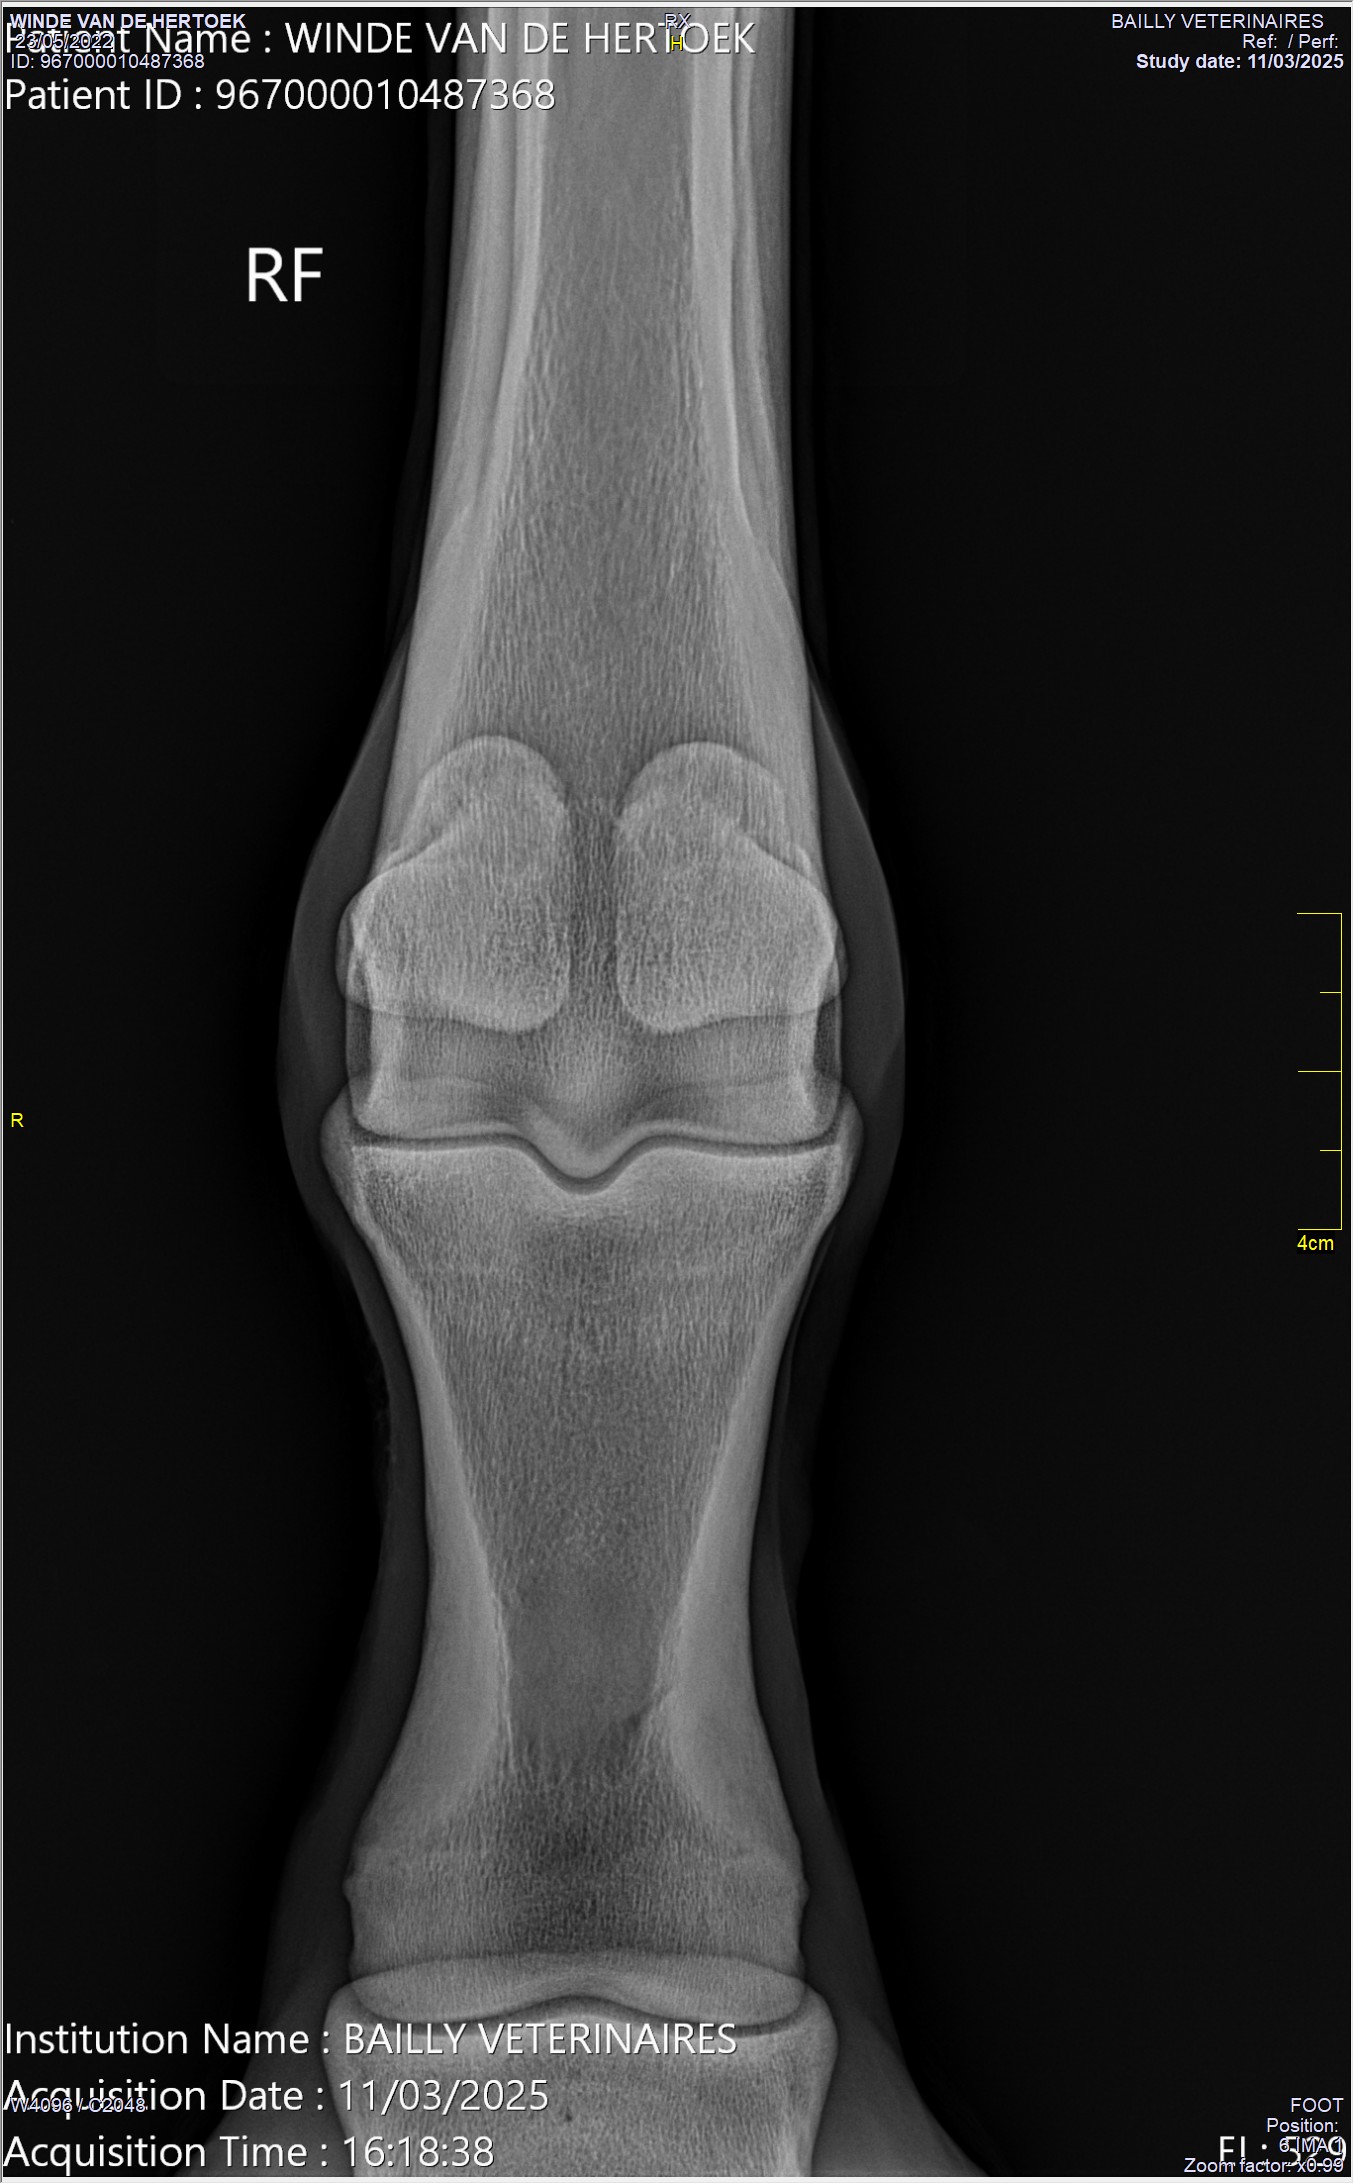

Radiographie Terminé

Dr. Martin Dupont

Bilan radiographique membres anterieurs

Serie de 4 cliches par membre anterieur. Absence de lesion osseuse ou articulaire significative. Remodelement articulaire MCP leger compatible avec l'age et le niveau de travail.